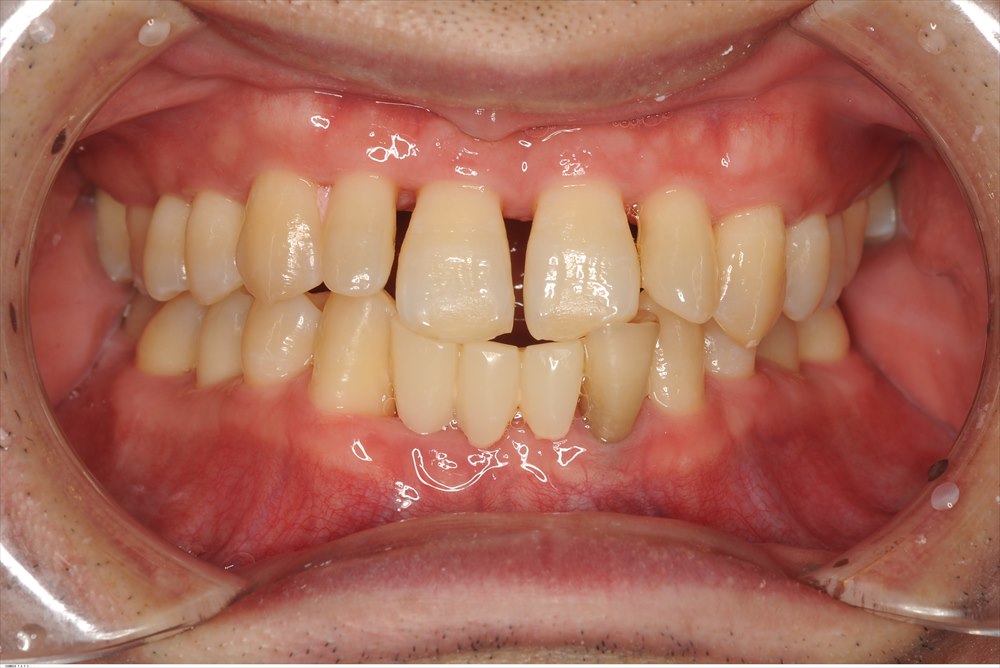

約1年半前に初診でいらした患者さま。重症の歯周病で来院されました。セカンドオピニオンです。

広範性・重度・侵襲性歯周炎と診断しました。

骨の量も全額的に少なく、下の前歯は抜けていました。

歯周初期治療(MINST)を徹底的に行いました。下記写真は初期治療後のデータです。